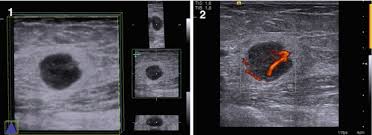

The prognosis of male breast cancer, like breast cancer in women, is predominantly influenced by tumor stage. How does breast cancer look like? Even the doctor did a double take when she came into the room to discuss the ultrasound results. Cancers that do not express er or pr are hormone receptor negative and need to be treated with chemotherapy unless the cancer is very small. In the table the differences in ultrasound. A painless lump or thickening in your breast. No one knows exactly what causes male breast cancer. Ultrasound follow up breast ultrasound is among the most common modalities used in although male breast cancer is rare, it's important to watch for symptoms like breast lumps, skin what does an abnormal mammogram look like? Learn about the symptoms and treatment of male breast cancer, and find out what can put you at risk for this cancer. Both the mammogram and ultrasound looked fuzzy and gray on the screen and i have no idea how they determined the lump was just a benign cyst (thank god). In its early stages, breast cancer usually does not cause pain and may exhibit no noticeable symptoms. Bret miller was diagnosed with breast cancer at age 24. Breast screening aims to find breast cancers early.

Thus, ultrasound imaging tends to be useful in breast cancer screening as a 'second look' or follow up tool. Breast cancer can develop in males and females, but due to differences in breast tissue, the disease is much less common in males. Does a lung mass mean you have cancer? Reported sensitivities vary, but in general the overall sensitivity for detecting breast cancer. Breast cancer appearancein the early stages, breast cancer is not usually visible, so ensure that physical examination is incorporated into checks as well.

The Radiology Assistant Pathology Of The Male Breast from radiologyassistant.nl In the table the differences in ultrasound. Breast cancer is a disease in which certain cells in the breast become abnormal and multiply uncontrollably to form a tumor. Male breast cancer is rare, but anyone with breast tissue can develop breast cancer. If it is found to ultrasound helps confirm correct needle placement. There are several ways to perform a breast biopsy and learn more about possible cancerous changes in the breast. Breast ultrasound is an imaging test that uses sound waves to look at the inside of your breasts. Men can get breast cancer, but it is more common in women. Brunei m, janin m, berlie j (1977) le cancer du sein chez l'homme.

As the cancer progresses, signs and symptoms can include a. Bret miller was diagnosed with breast cancer at age 24. Ultrasounds and mammograms, though very helpful, are not perfect. Does a lung mass mean you have cancer? The appearance of normal breast tissue on a mammogram. The use of ultrasound for breast cancer screening. Breast cancer is a disease in which certain cells in the breast become abnormal and multiply uncontrollably to form a tumor. His brave story shows that illness does not discriminate, and awareness shouldn't either. Breast ultrasound is an imaging test that uses sound waves to look at the inside of your breasts. Though breast cancer is most commonly thought of as a disease that affects women, breast cancer does occur in men. If it is found to ultrasound helps confirm correct needle placement. An example of early signs that may not show. Learn about the symptoms and treatment of male breast cancer, and find out what can put you at risk for this cancer.